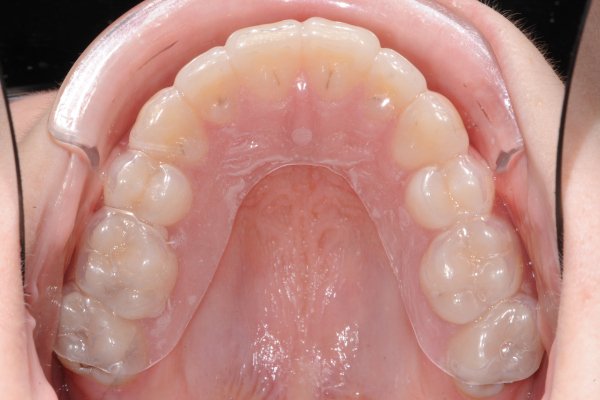

Essix splint

The Essix splint is removable. Unless otherwise instructed, the Essix splint is used every night for the first year. Thereafter, the use is reduced by using the Essix splint every other night for six months, followed by further reduction. Two years after the braces have been removed, you use the Essix splint 1-2 nights a week. If you want your teeth to remain in the position they are in after treatment, you need to use the essix splint 1-2 nights a week as long-term retention.

The Essix rail is cleaned with a toothbrush and lukewarm water. It is delivered in a box which also needs to be cleaned occasionally. It is important to keep the splint in the box when not in use and out of reach of any pets. If the splint is lost, you will be responsible for the cost of a new splint.

Take the rail with you at every inspection!

Extra cleaning if necessary

Deposits on the splint can be removed by placing it in a glass of water with 2 tablespoons of vinegar (or a Coregate tablet), leave it for about 1 hour, then clean it as usual with a brush and lukewarm water.